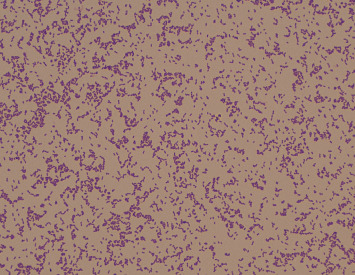

Slackia exigua is an anaerobic, Gram-positive, nonspore-forming bacterium that is typically part of the normal oral microbiota. It is generally considered biochemically inert and is often dismissed as a nonpathogenic contaminant in clinical cultures, particularly in respiratory samples. However, in this case study, we report a rare instance of S. exigua bacteremia in a patient with multiple medical comorbidities who was hospitalized after reporting to Emergency Department due to fatigue and right ear pain. The patient subsequently developed signs of persistent symptoms of septicemia, prompting an extensive investigation. Blood cultures identified S. exigua as the causative agent. This case underscores the importance of thorough culture workup and clinical correlation, especially in immunocompromised patients and patients with multiple medical comorbidities. Comprehensive dental care and the administration of targeted antibiotic therapy resulted in the patient's full recovery. This report highlights the potential pathogenic role of S. exigua in certain clinical scenarios and emphasizes the need for awareness of its possible implications in systemic infections.

Abstract Image